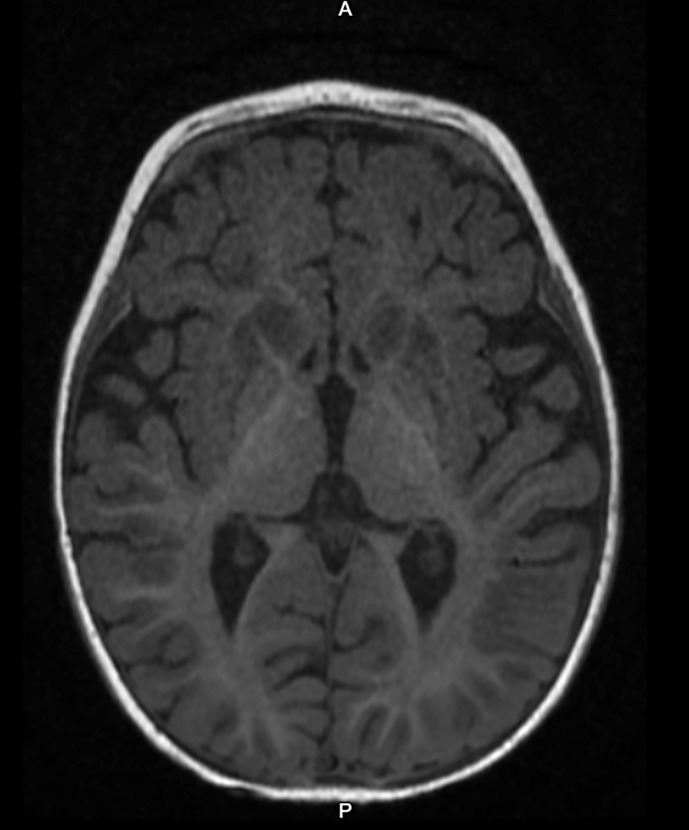

Case presentation: Our case is a 7-month-old female infant who presented with a 3-week history of irritability, altered behavior, and refusal of newly introduced solid foods. Symptoms started with an upper respiratory tract infection, followed by lethargy, floppiness, and abnormal movements. The patient was admitted to the pediatric ward with a broad differential diagnosis. Extensive laboratory evaluations revealed lactic acidosis. MRI brain showed symmetric restricted diffusion affecting the bilateral basal ganglia, thalami, and cortical regions. Whole genome sequencing identified biallelic variants of the SLC19A3: a c.1364T>G p.Met455Arg missense variant in the maternal allele and a 2.3 kb deletion of intron 3 of the paternal allele. Both variants were identified as variants of uncertain significance. However, given the clinical picture, MRI brain findings, resolution of symptoms with empiric biotin and thiamine supplementation, and biallelic SLC19A3 variants of unknown significance, the patient most likely suffers from BTBGD. Patient continues to show sustained developmental progress on biotin and thiamine supplementation.